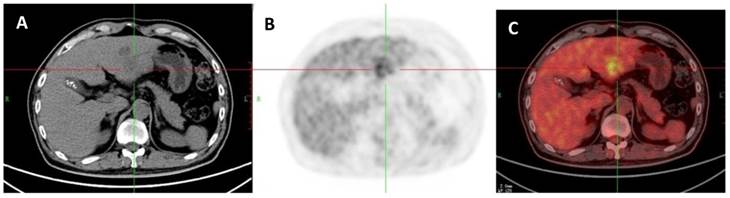

Figure 6

A 51-year-old woman with liver abscess which was proved by liver biopsy. A: Axial non-contrast CT-scan showed a low density lesion in right lobe; B: 18FDG PET image showed high ring uptake in the lesion than liver background (SUVratio=4.1); C: Axial 18FDG PET/CT fusion image.

The ROC curves and AUC of SUV ratio in younger group are shown in Figure 2. ROC analysis showed that the optimal cut-off value in these patients was 1.17 for SUV ratio and 0.962 for AUC. The younger patients group showed the highest sensitivity and specificity, followed by the older group, and the middle-aged group. Typical 18FDG-PET/CT imaging examples of benign and malignant solitary liver lesions in this group are displayed in Figure 3 and 4. Figure 3 showed a female patient with liver cyst where the SUV ratio was 0.3, and Figure 4 showed a male patient with HCC of which the SUV ratio was 2.1. The ROC curves and AUC of SUV ratio in middle-aged group are shown in Figure 5. ROC analysis showed that the optimal cut-off value in all patients was 1.45 for SUV ratio and 0.650 for AUC. The middle-aged group revealed the lowest sensitivity and specificity. Typical 18FDG-PET/CT imaging examples of benign and malignant solitary liver lesions in this group are displayed in Figure 6 and 7. In Figure 6 from a female patient with liver abscess, the SUV ratio was 4.1, which was much higher than the optimal cut-off value. On the other hand, in figure 7 from a male patient with HCC, the SUV ratio was only 0.98. The ROC curves and AUC of SUV ratio in elderly group are presented in Figure 8. ROC analysis showed that the optimal cut-off value in these patients was 1.25 for SUV ratio and 0.973 for AUC. The elderly group yielded relatively high sensitivity and specificity. Typical 18FDG-PET/CT imaging examples from a patient with benign and malignant solitary liver lesions in this group are demonstrated in Figure 9 and 10, respectively.